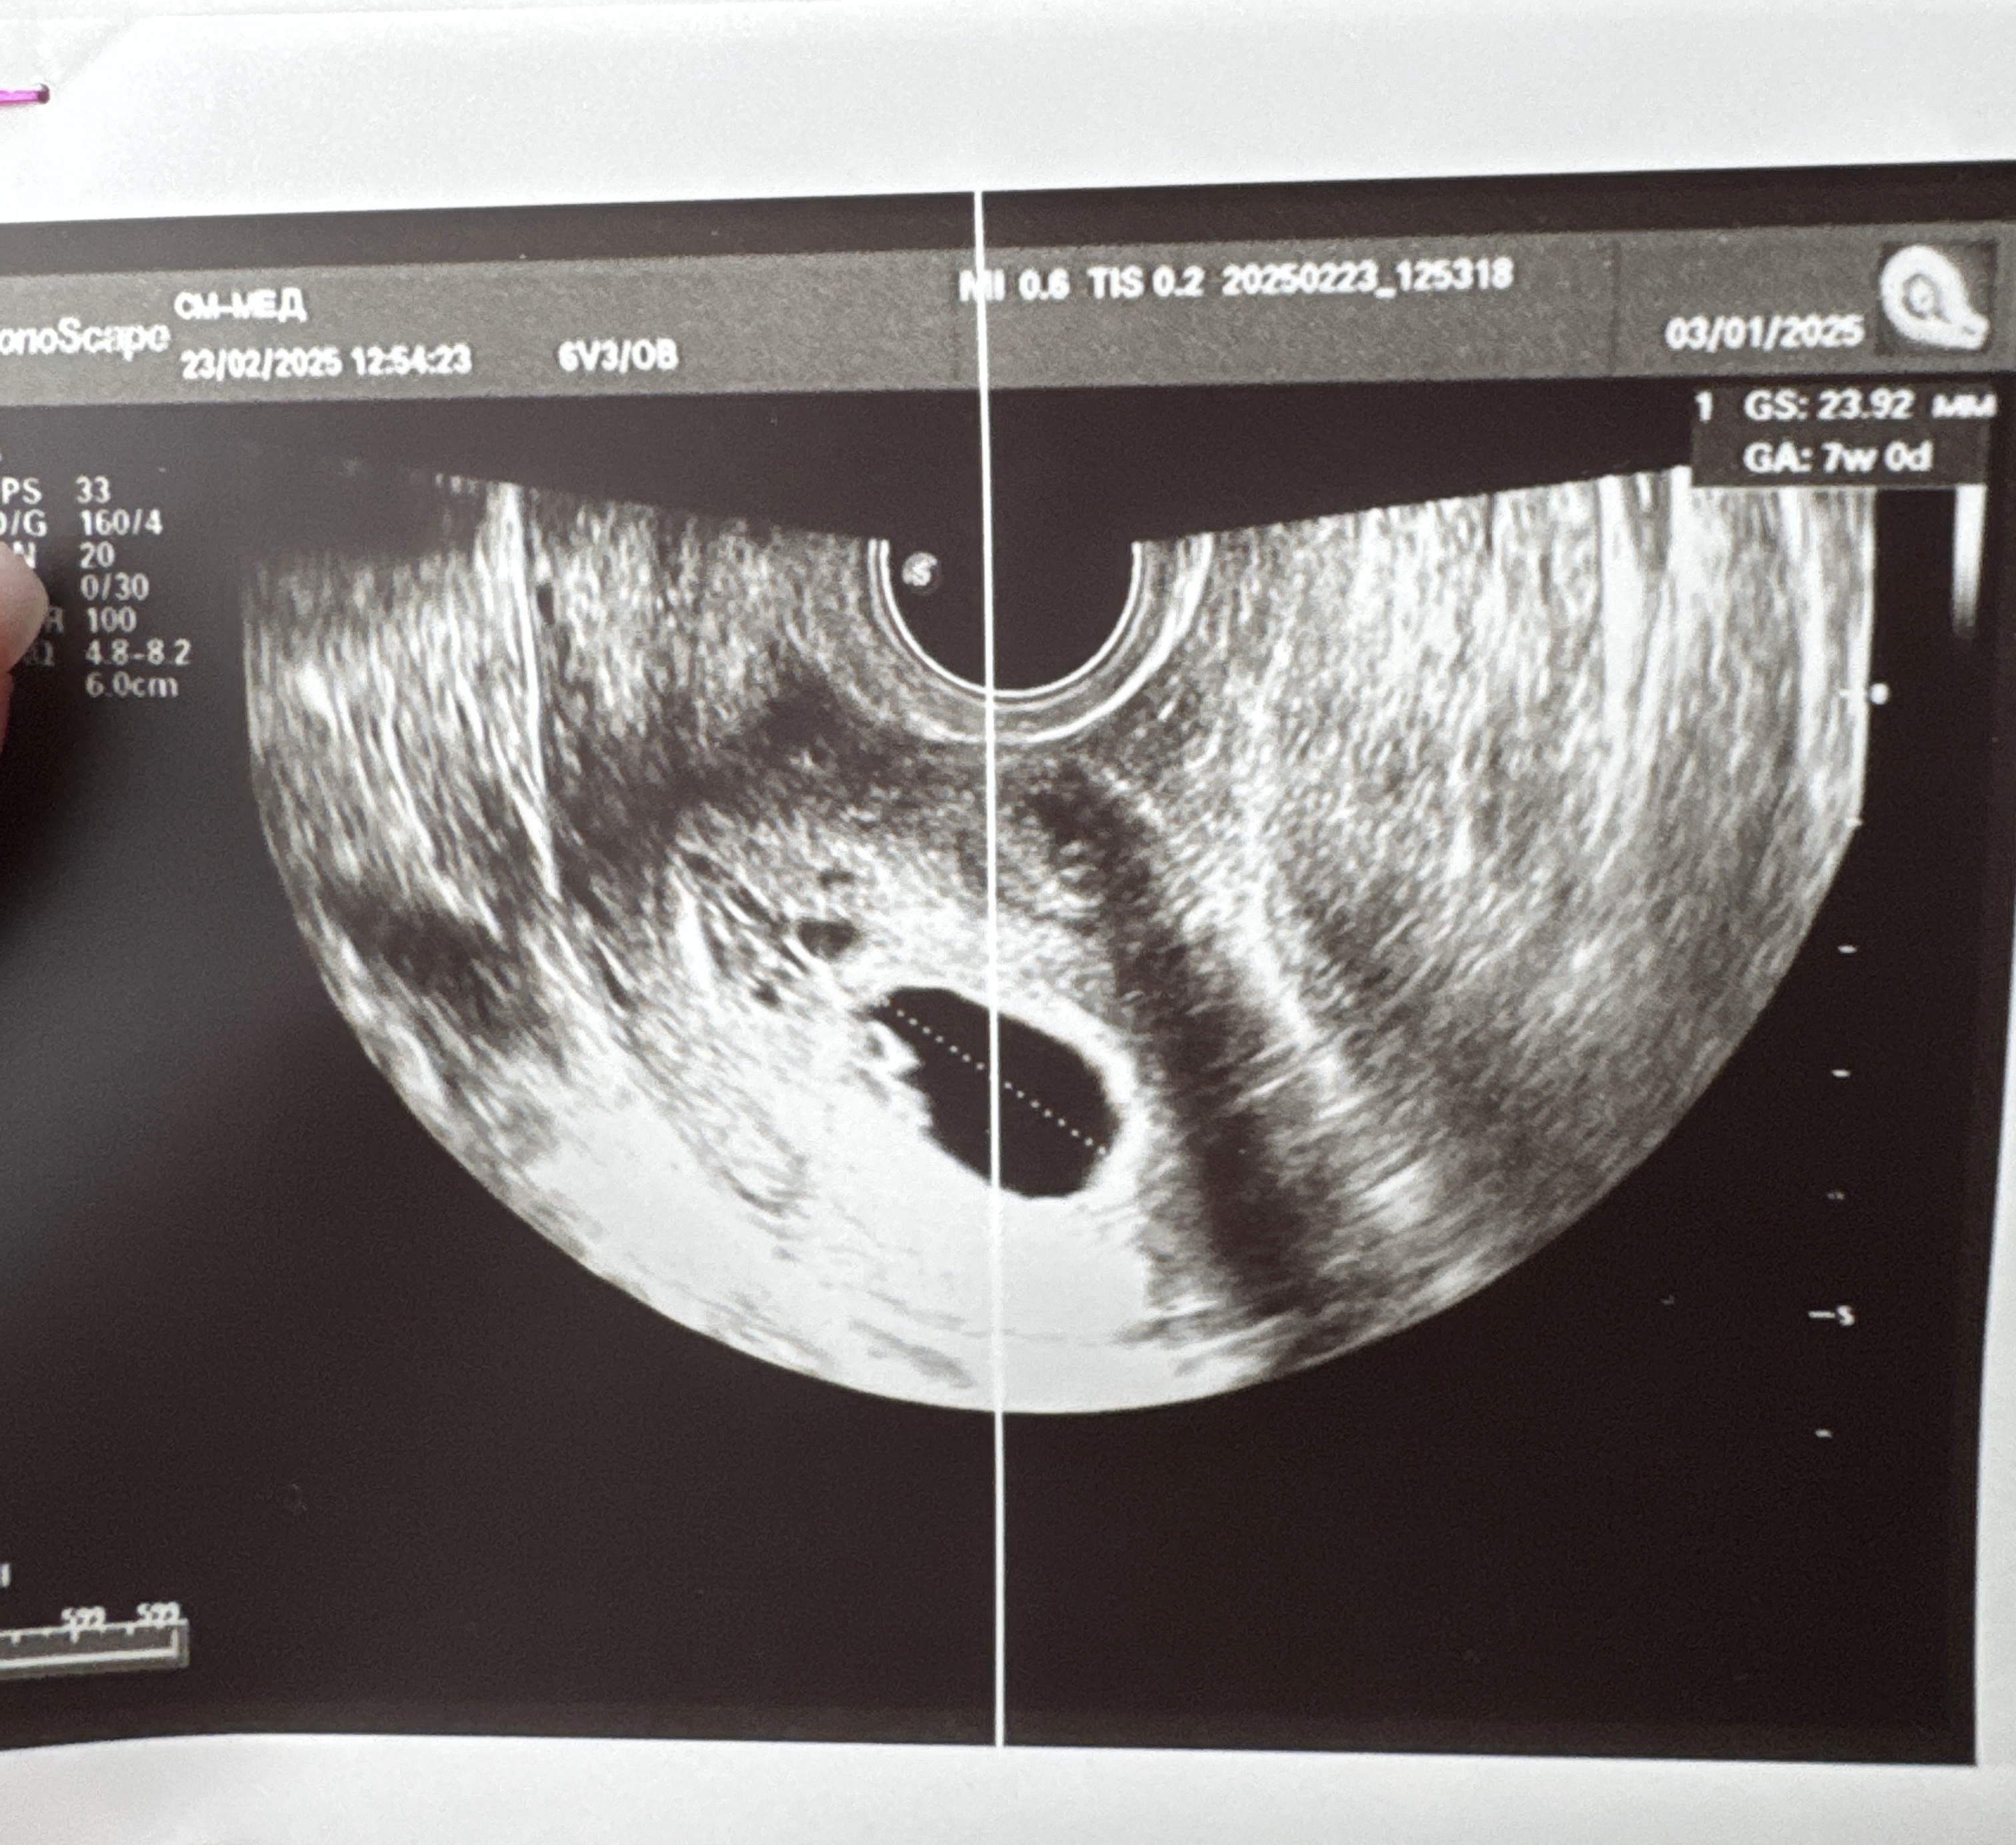

7 недель (6 недель 4 дня)

По узи все в порядке, срок соответствует 6недель и 4дня, с учетом погрешности моей овуляции все совпадает (6-7 недель ставит мне приложение). Сердечко крохотное, но такое трепещущее. Была на 7 небе от счастья, что все в порядке и со мной и с этой крошкой.